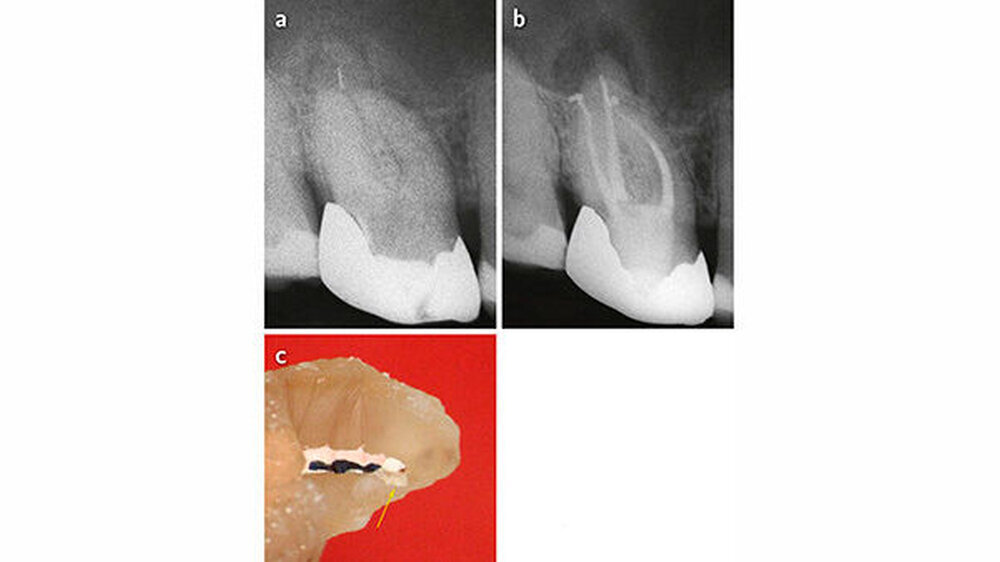

Die langfristige Prognose für einen Zahn nach Instrumentenfraktur ist abhängig vom Grad der Infektion und vom Zeitpunkt der Instrumentenfraktur (Simon et al. 2008; Ungerechts et al. 2014). Je später die Fraktur passiert, desto größer die Wahrscheinlichkeit, dass der Kanal chemomechanisch schon gut aufbereitet ist und demzufolge weniger Mikroorganismen und/oder nekrotisches Gewebe vorhanden sind (Abb. 3). Je fortgeschrittener die Infektion (entzündete Pulpa, nekrotische Pulpa, periradikuläre Aufhellung), desto mehr und tiefer im Kanal liegende Mikroorganismen sind zu erwarten. Außerdem sind bei Revisionen tendenziell resistentere Keime zu erwarten als bei Ersteingriffen.